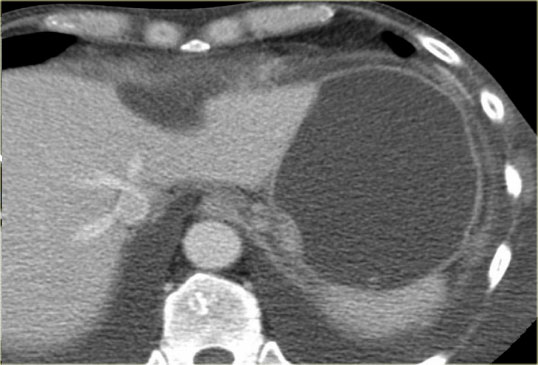

The CT demonstrates a large cyst in the upper abdomen in a patient who had an acute pancreatitis (Fig).

Notice that there is also some ascites and pleural fluid.

There is wall enhancement.

Most pseudocyst occur in the peripancreatic region, but rarely they may extend to the mediastinum.

Scroll through the images.

This patient has a chronic pancreatitis.

Notice the calcifications in the pancreatic head (curved arrow).

There are multiple pseudocysts extending all the way to the mediastinum compressing the heart (red arrow).